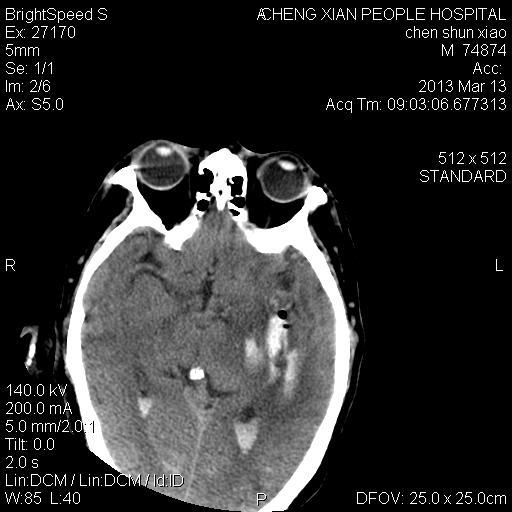

患者陈++,男,71岁。因“昏迷四小时,伴右侧肢体活动受限”以“脑出血”收住院。发病后12小时用“改良立体定向-软通道微创介入新技术治疗脑出血”。术后24小时颅内出血大部被清除,患者神志清晰。右侧肢体肌力0级。

患者陈++,男,71岁。因“昏迷四小时,伴右侧肢体活动受限”以“脑出血”收住院。发病后12小时用“改良立体定向-软通道微创介入新技术治疗脑出血”。术后24小时颅内出血大部被清除,患者神志清晰。右侧肢体肌力0级。